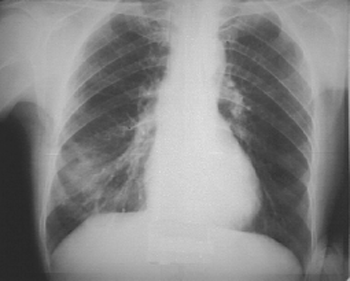

Инструментальные данные. Рентгенологическое исследование позволяет уточнить локализацию и размеры воспалительной инфильтрации, которая определяется, как участок затемнения без четких контуров (рис. 2).

Рис. 2. Пневмония в правом легком